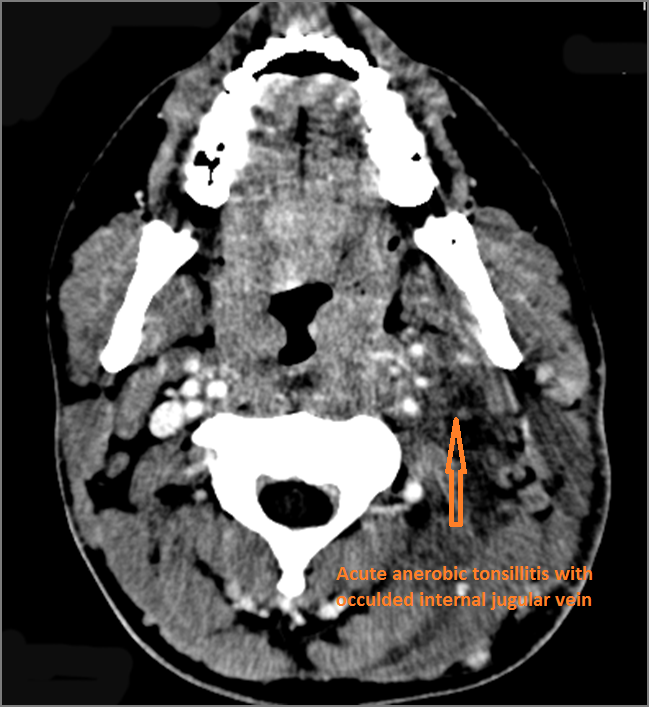

Vascular Findings

There is evidence of thrombus, thrombophlebitis or other occlusive or inflammatory process of the jugular vein. [Yes/No]

There is evidence of thrombus, thrombophlebitis or other occlusive or inflammatory process of smaller jugular venous tributaries. [Yes/No]